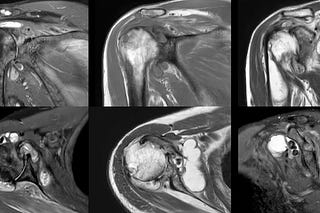

Case of the Day - 091 - 2025 08 26 - How Many Signs of an Intramuscular Schwannoma?

34-years old with pain along the medial and posterior aspects of the proximal leg with a positive Tinel sign.